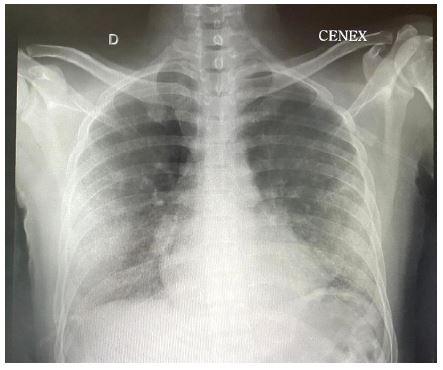

Los exámenes auxiliares proporcionan hemograma con leucocitos: 10 650/mm3, plaquetas: 321 000/mm3, hemoglobina: 6,9 g/dl, volumen corpuscular medio: 87,4 fL, hemoglobina corpuscular media: 29,9 pg. Los exámenes bioquímicos, bilirrubina total: 0,40 mg/dl, bilirrubina directa: 0,10 mg/dl, creatinina: 0,58 mg/dl, urea: 40 mg/dl, deshidrogenasa láctica: 233 UI/L, proteína C reactiva: 2,7, ferritina: 116 mg/dl, dímero D: 1,02 µg/ml, ELISA-VIH I-II: no reactivo, prueba ARN para SARS-CoV-2 en muestra respiratoria por RT-PCR en tiempo real: negativo, prueba rápida antigénica COVID-19: no reactiva, baciloscopia directa para Mycobacterium tuberculosis en orina, heces y esputo: negativos. Radiografía de tórax posteroanterior: patrón alveolointersticial periférico a predominio bibasal; radiografía de tórax (Figura 1), tomografía espiral multicorte con contraste de tórax: áreas de vidrio delustrado periférico respetando área central (Figura 2); tomografía espiral multicorte con contraste de región glútea (Figura 3): nódulos granulomatosos a cuerpo extraño asociados a signos inflamatorios en plano graso subcutáneo de la región glútea y muslos proximales derecho e izquierdo. Recibió oxacilina y clindamicina endovenosas por sospecha de infección de partes blandas en lugar de inyección, anticoagulación terapéutica por sospecha de tromboembolismo, corticoterapia durante 9 días y soporte oxigenatorio. La evolución fue favorable, por lo que fue dado de alta después de 10 días.

De acuerdo con la literatura, las edades de los casos varían entre los 20 a 55 años, y se presentan con mayor frecuencia en el sexo femenino; en menor cuantía, en los varones transexuales. Respecto a la clínica de presentación, va desde dificultad respiratoria, dolor torácico de tipo punzante u opresivo, fiebre, tos seca (1,5,7-10,11,12,13 y hemoptisis 14; así mismo, la presentación puede ser aguda, dentro de las primeras 24 horas tras la inyección, y latente, en donde se reportan casos de hasta 13 meses. La cantidad de geles de silicona inyectada repercute en el inicio de los síntomas, y se describe que desde 100 ml de inóculo a más puede presentarse en forma aguda 4. Al ingreso, se han reportado distintos grados de hipoxemia en los análisis de gases arteriales 1,4,7,15. Las imágenes encontradas en las radiografías de tórax al ingreso van desde una radiografía normal 2, un patrón alveolar difuso 13,15, reticular difuso bilateral 4,8,9, alveolar difuso bibasal y periférico 1,3, este último presente en nuestro caso; las tomografías de tórax computarizadas, de acuerdo con los informes, mostraron al ingreso áreas de consolidación a predominio bibasal 9,15, en parches y áreas en vidrio deslustrado periférico 3,4,8,13, algunos con broncograma aéreo (1y) de nódulos pulmonares no clasificados; la predominancia del compromiso periférico en vidrio deslustrado respetando el área central presente en nuestro caso, que según Soeroso cataloga como muy "sugerente de inyección de silicona líquida". Asimismo, se planteó la sospecha de tromboembolismo pulmonar; sin embargo, fue descartado dada la probabilidad clínica baja luego de aplicar la regla de predicción clínica de Geneva y el score de Wells, por lo que no se justificó realizar otro examen diagnóstico más específico.